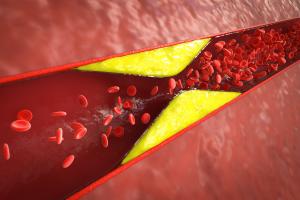

ATHÉROSCLÉROSE : Réaliser les promesses des sphingolipides

MALADIE CORONARIENNE : Une petite pilule contre les lipoprotéines ?

Actualité publiée le 27/09/2023CHOLESTÉROL : Une marge d’amélioration considérable des traitements

LIPOPROTÉINE A : Une métrique plus sensible que le mauvais cholestérol LDL

ATHÉROSCLÉROSE : Le gène qui pourrait prévenir la crise

ATHÉROSCLÉROSE : Lutéine vs inflammation